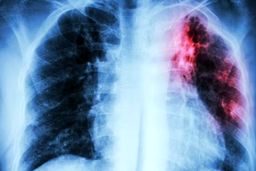

شیوع دوباره سل در جهان از پیامدهای کرونا شناخته شد.

خبرمهم: شیوع دوباره سل در جهان از پیامدهای کرونا شناخته شد.

کووید ۱۹ عامل افزایش موارد ابتلا به سل در جهان

خبرمهم: پزشکان در یک مطالعه تازه هشدار دادند که محدودیتها و اعمال قرنطینههای خانگی با هدف مهار همهگیری کووید ۱۹ با…